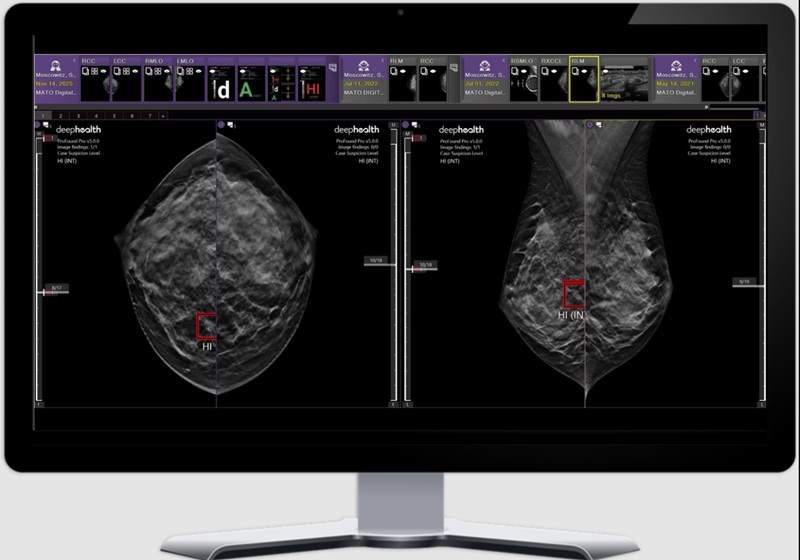

Sistema de imagen bioinspirado identifica ganglios linfáticos cancerosos de forma intraoperatoria